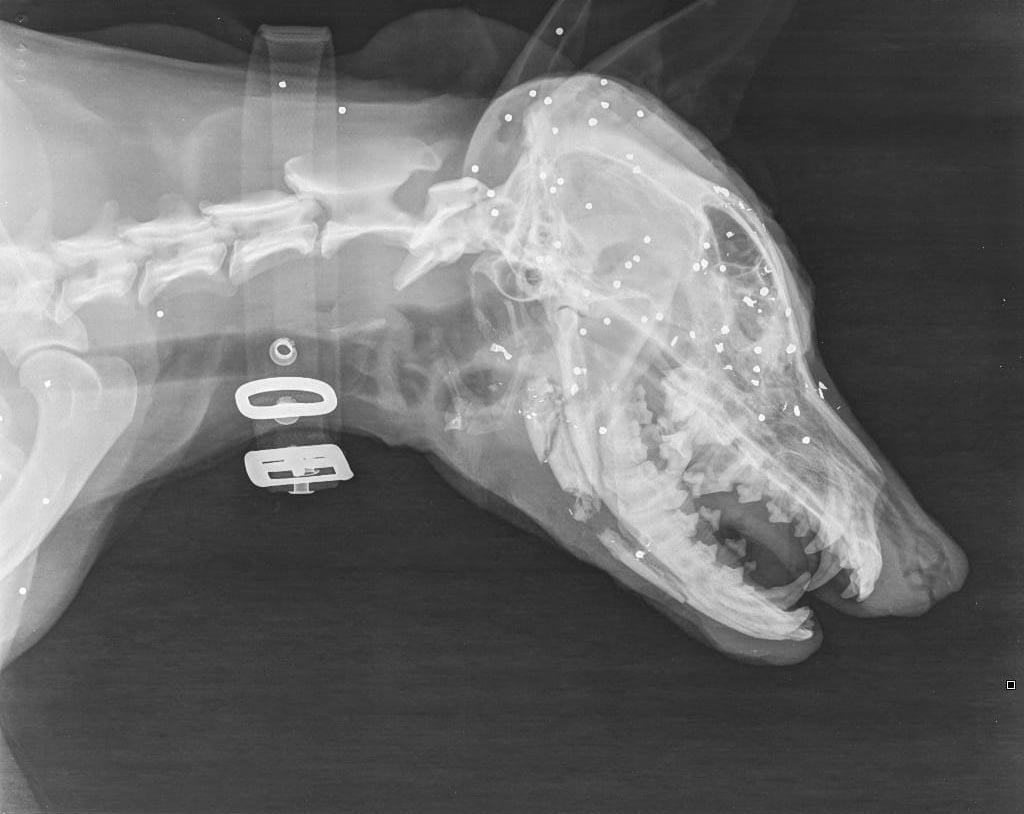

Ήταν πυροβολημένο στο πρόσωπο με καραμπίνα εξ επαφής, είχε διαλυθεί η γναθος, είχε πολλαπλές κρανιοεγκεφαλικες κακώσεις και η κατάστασή του ήταν ιδιαίτερα κρίσιμη.

Υπήρχε και δεύτερος πυροβολισμος στη σπονδυλικη στήλη.

Δόθηκαν οι πρώτες βοήθειες με την ελπίδα να σταθεροποιηθει, στείλαμε ακτινογραφιες σε κτηνιατρους, ώστε μετά να συζητηθεί τι χειρουργικές επεμβάσεις θα χρειαστούν.